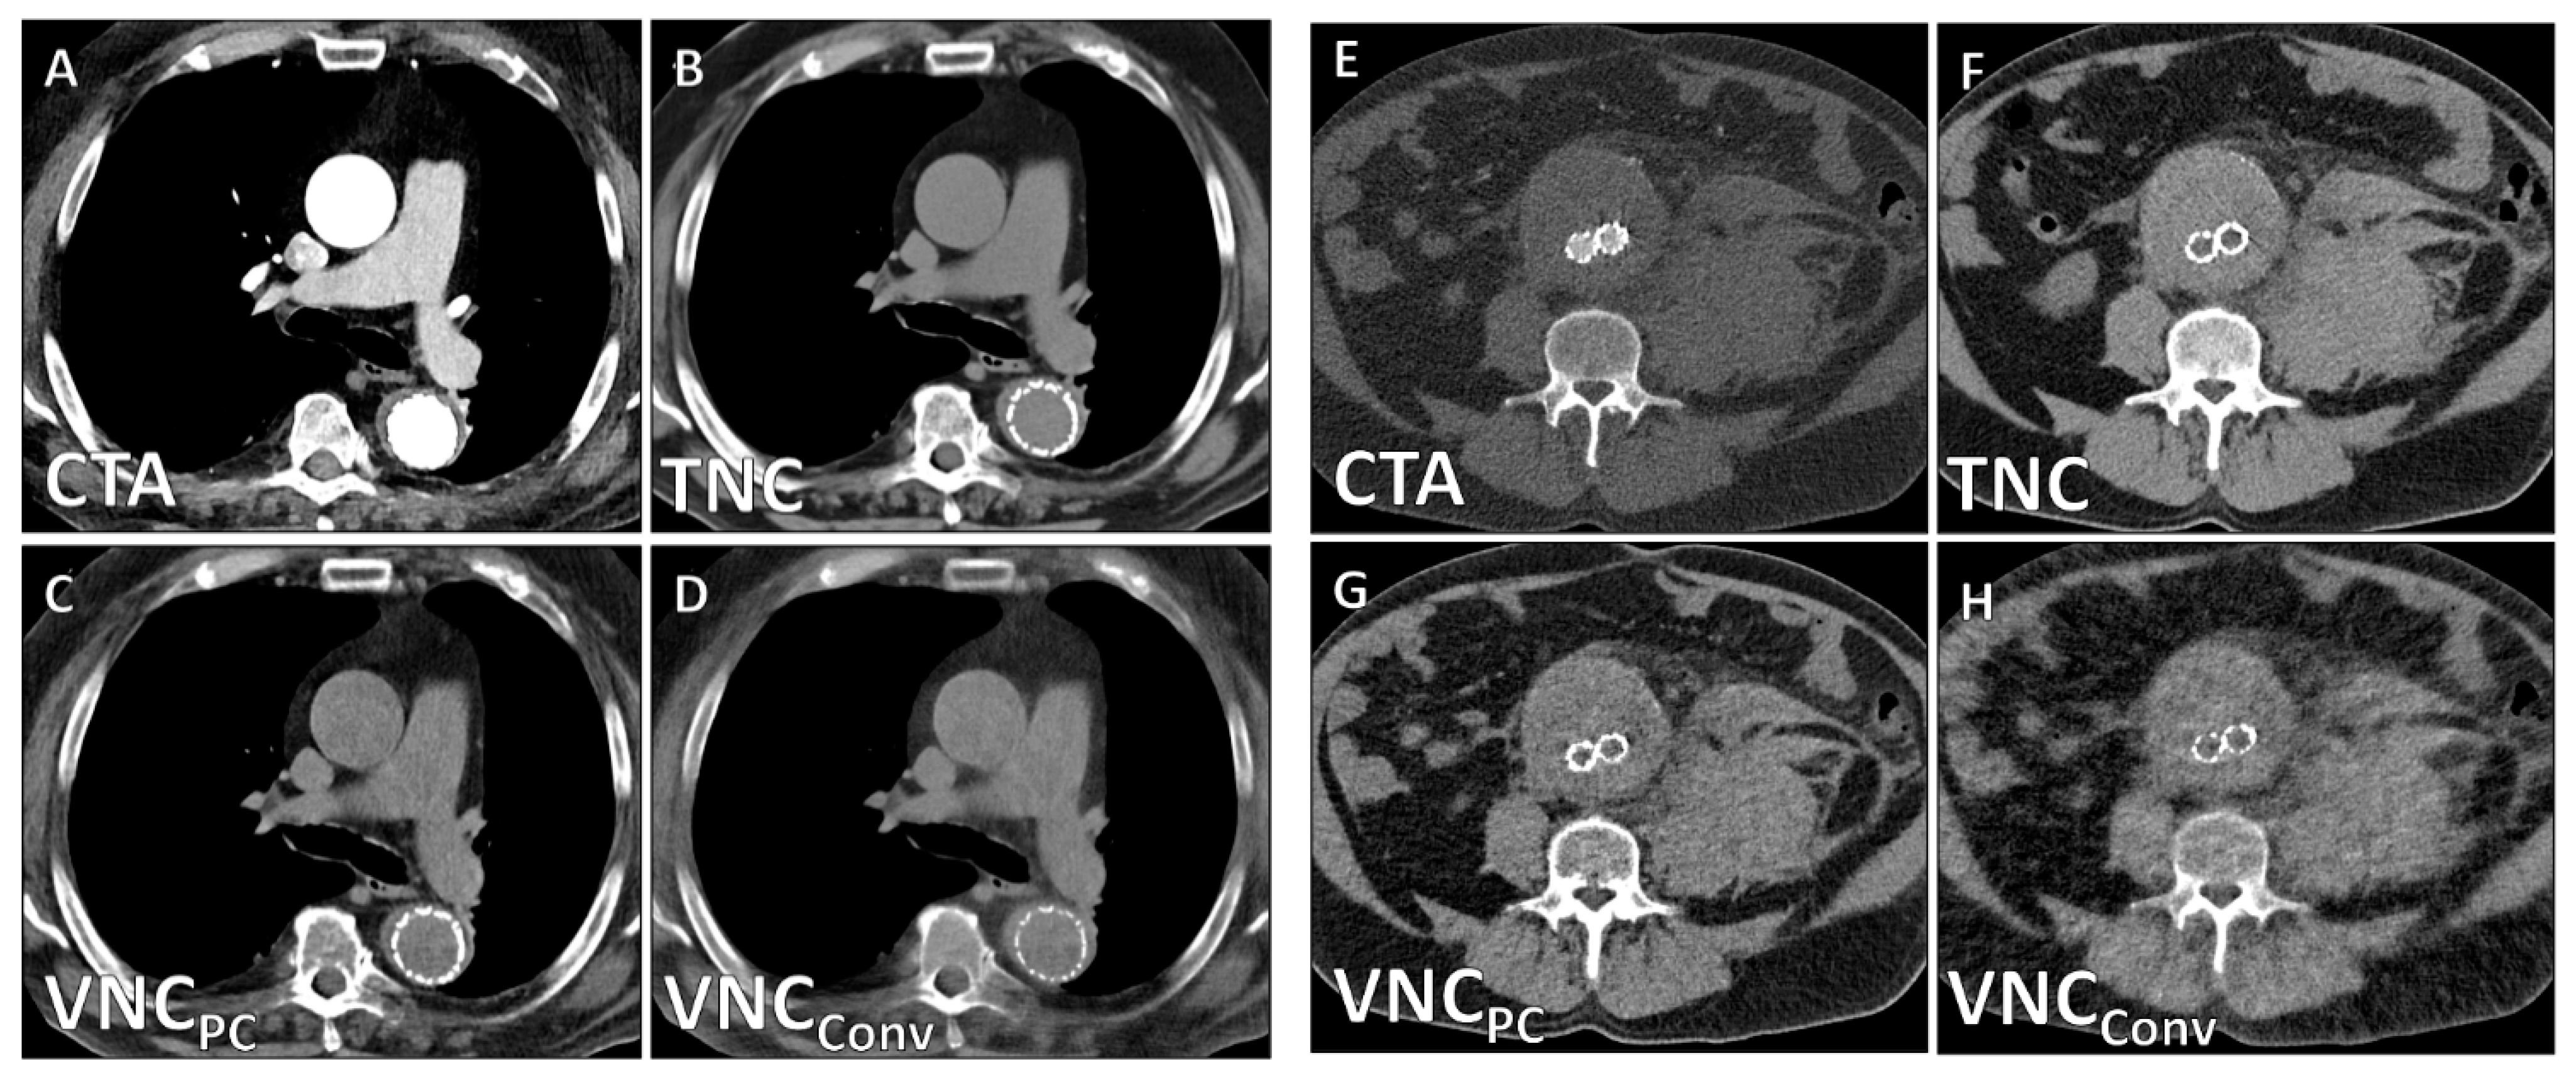

| TNC | VNCPC | VNCConv | Friedman X2 | p | Subgroup Analysis | p | |

| CT values/HU | 44.4 ± 15.5 | 39.1 ± 15.8 | 33.2 ± 15.9 | 19.6 | 0.006 | TNC/VNCPC TNC/VNCConv VNCPC/VNCConv | 0.013 <0.001 <0.001 |

| Noise/HU | 14.9 ± 7.1 | 16.7 ± 7.1 | 18.6 ± 5.3 | 22.8 | 0.003 | TNC/VNCPC TNC/VNCConv VNCPC/VNCConv | <0.001 <0.001 0.021 |

| SNR | 3.3 ± 1.6 | 2.5 ± 1.3 | 1.9 ± 0.9 | 25.0 | <0.001 | TNC/VNCConv TNC/VNCConv VNCPC/VNCConv | <0.001 <0.001 <0.001 |

| Image Quality | 4.2 ± 0.9 | 0.68 (0.44–0.78) | 2.5 ± 0.6 | 0.62 (0.43–0.77) | <0.001 |

| Calcium Subtraction | 4.6 ± 0.5 | 0.75 (0.66–0.82) | 3.0 ± 0.6 | 0.58 (0.40–0.71) | <0.001 |

| Stent Subtraction | 4.7 ± 0.7 | 0.72 (0.58–0.81) | 3.8 ± 1.2 | 0.62 (0.49–0.77) | 0.003 |

| Contrast Subtraction Aorta | 5.0 ± 0.0 | 1.0 (1.0–1.0) | 5.0 ± 0.0 | 1.0 (1.0–1.0) | 1 |

| Contrast Subtraction Total | 4.3 ± 0.8 | 0.86 (0.71–0.95) | 4.0 ± 1.1 | 0.79 (0.66–0.89) | 0.091 |